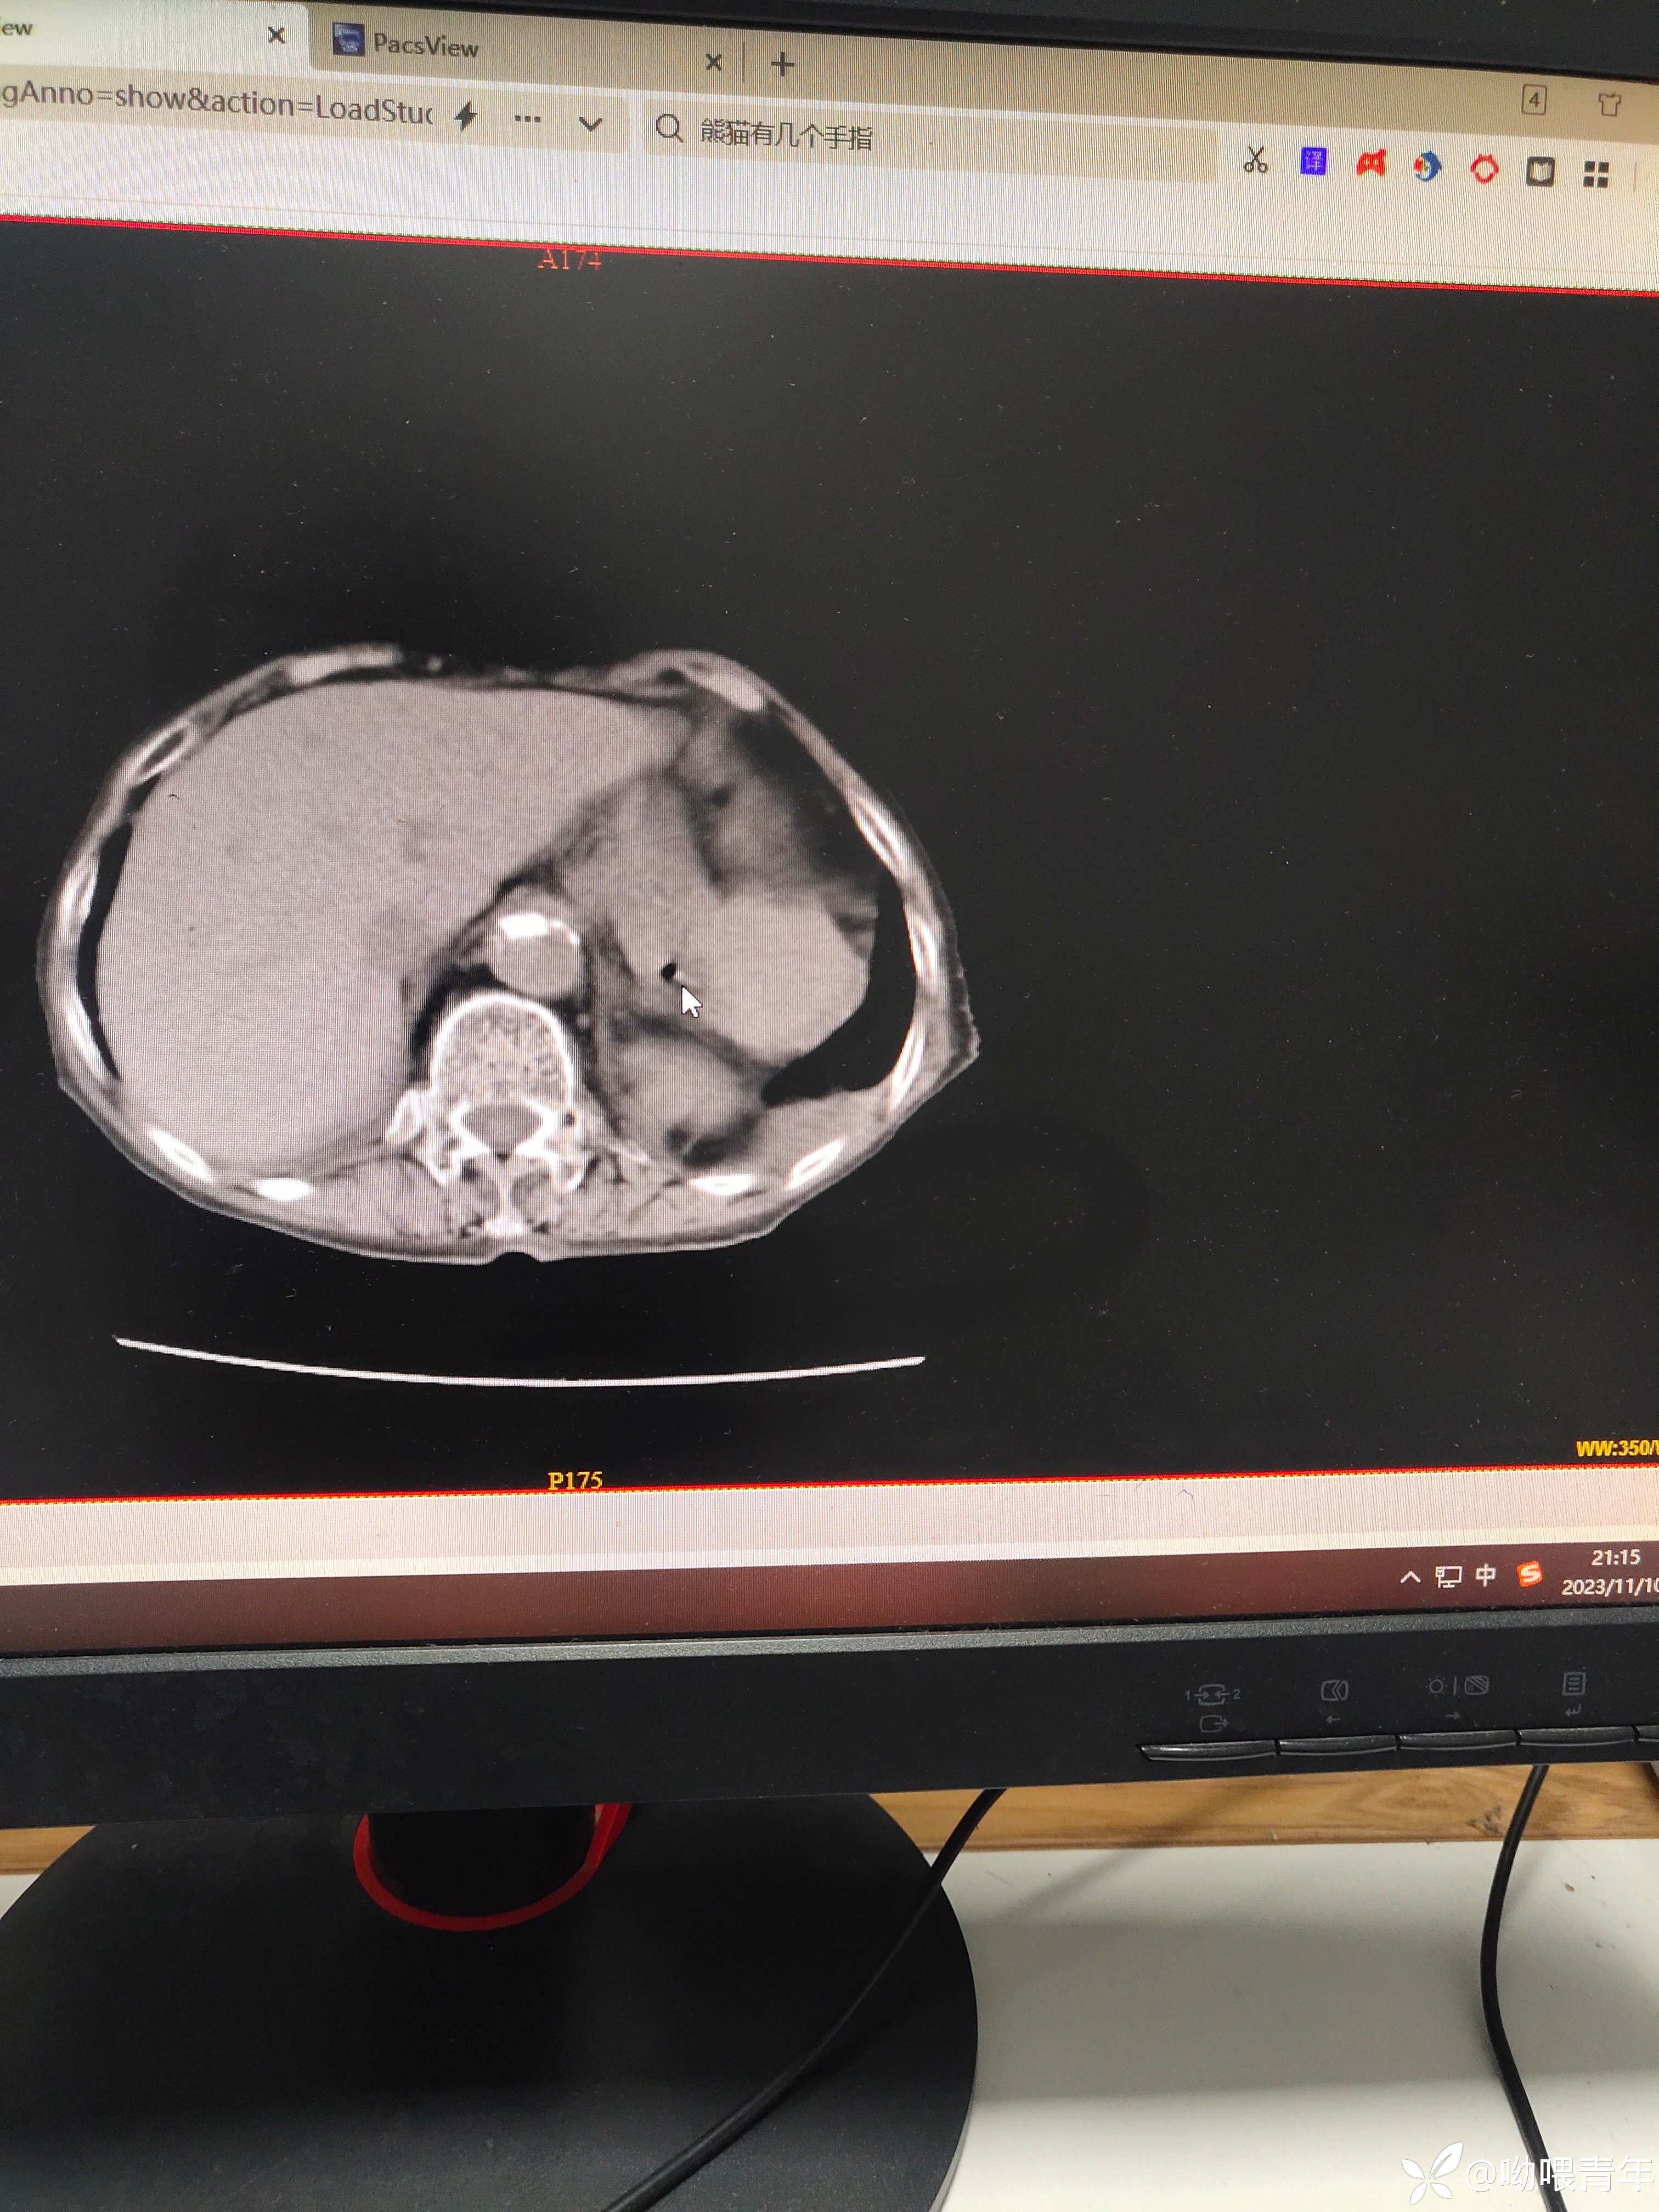

90多岁病人,右腹痛2天急诊入院,行上腹部CT检查提示:1.胆囊形态增大伴泥沙样结石;2.消化道穿孔可能。感染指标正常。查体:体温正常,查体腹肌紧张,右侧腹部轻压痛,无反跳痛。请各位老师帮忙分析一下。